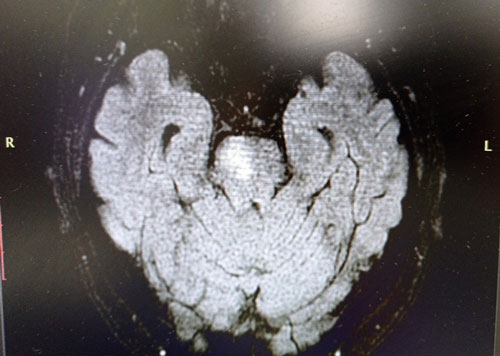

Данные магнитно-резонансной томографии пациентов с этими видами патологии представлены на рис. 1 и 2.

Рис. 1. Пациент В., передняя трифуркация левой внутренней сонной артерии, магнитно-резонансный сигнал от правой задней соединительной артерии отсутствует, низкоинтенсивный сигнал от правой передней мозговой артерии

Рис. 2. Пациент В., очаг ишемии в области моста (вертебробазилярный бассейн)